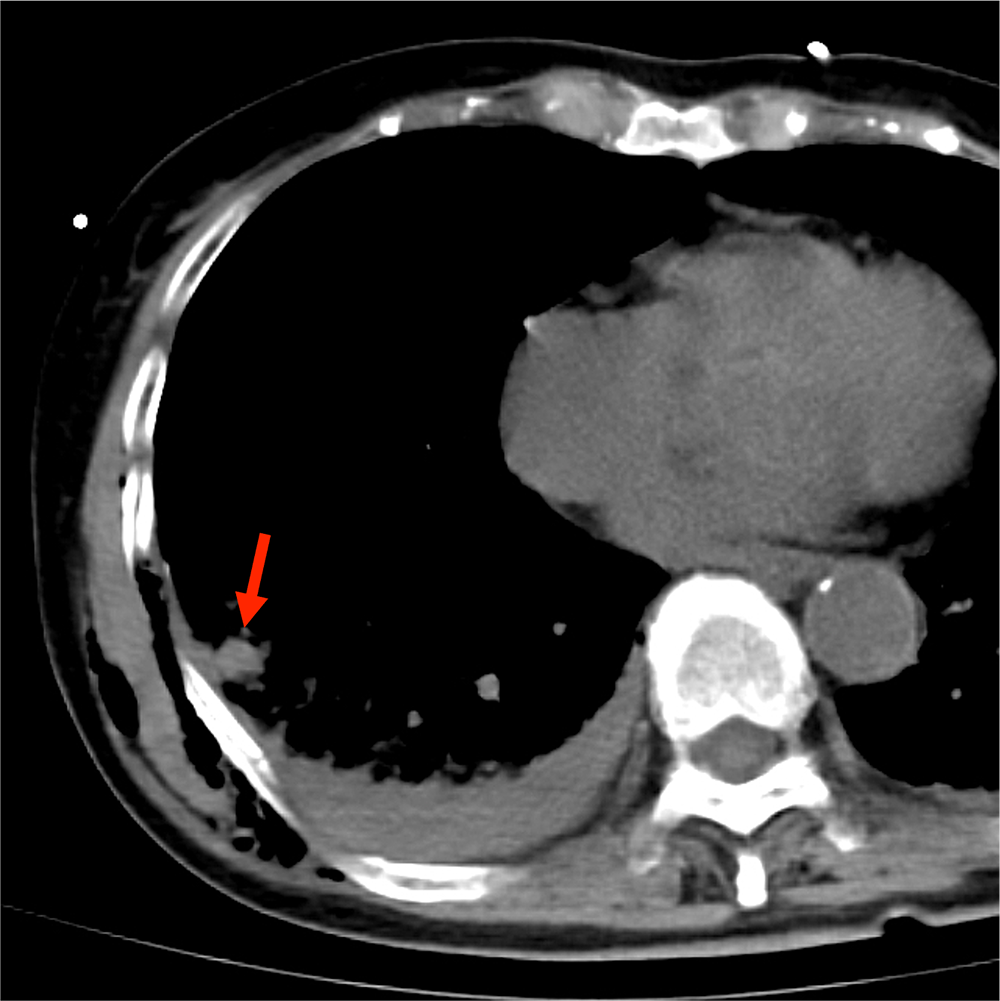

外傷性血気胸による肺内血管外漏出

80歳代、女性、42kg、外傷性血気胸、肺挫傷

CTでは多発肋骨骨折、外傷性血気胸、肺挫傷、胸壁内気腫が認められた。

挫傷した肺内には結節状構造がみられ、肺気瘤の形成が示唆される。造影CTではこの内部に点状の濃染影が認められ、肺実質内血管外漏出(extravasation in the lung:EVIL)が疑われた。

肺挫傷や血気胸は単純CTでも確認できるが、造影CTを追加することで肺内血管外漏出(EVIL)の有無を確認することができる。

血管外漏出は活動性出血の存在を示唆する兆候で、外傷時のCTではまず確認すべき重要な所見である。腹部や骨盤部での血管外漏出は直ちに手術やIVRの適応になることが多いので、読影の際に見落としてはならない所見として認知されているが、肺挫傷で血管外漏出の有無を確認することの重要性はあまり知られていない。

肺挫傷では肺組織に含まれる組織因子が血管内に遊離することで凝固外因系の活性化が生じる。これによりトロンビンの活性化からフィブリン血栓形成が始まり、二次線溶反応が起こる。肺挫傷の場合は出血だけでなく、ショックやアシデミア、低体温が加わりやすく、線溶反応の亢進や著明な出血傾向に陥りやすくなる。つまり広範な肺挫傷やEVILを認めた場合には、凝固破綻に移行しやすくなることを想定して治療にあたる必要がある。